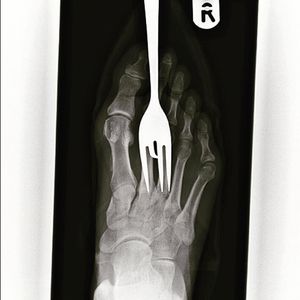

Foot fork-stabbing injury, better watch your steps!

Sensitive

Xray

Injury

Foot